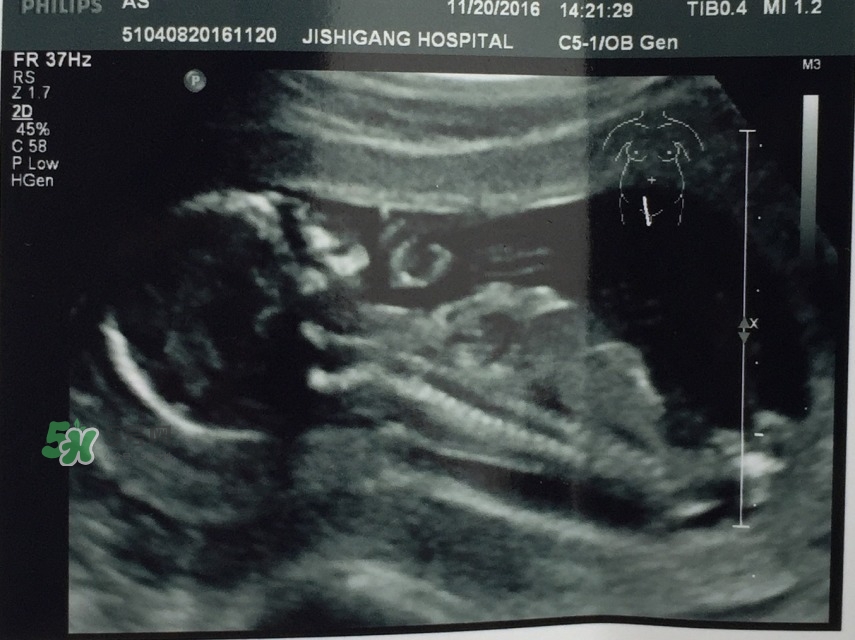

* 2016年11月20日孕15w

建卡后第一次孕檢,B超,尿檢,醫(yī)生說太早吃鈣片,停吃10天

* 2017年1月15日孕23w+2

愛博爾四維彩超,愛吃手指、愛摸屁屁的萌寶寶